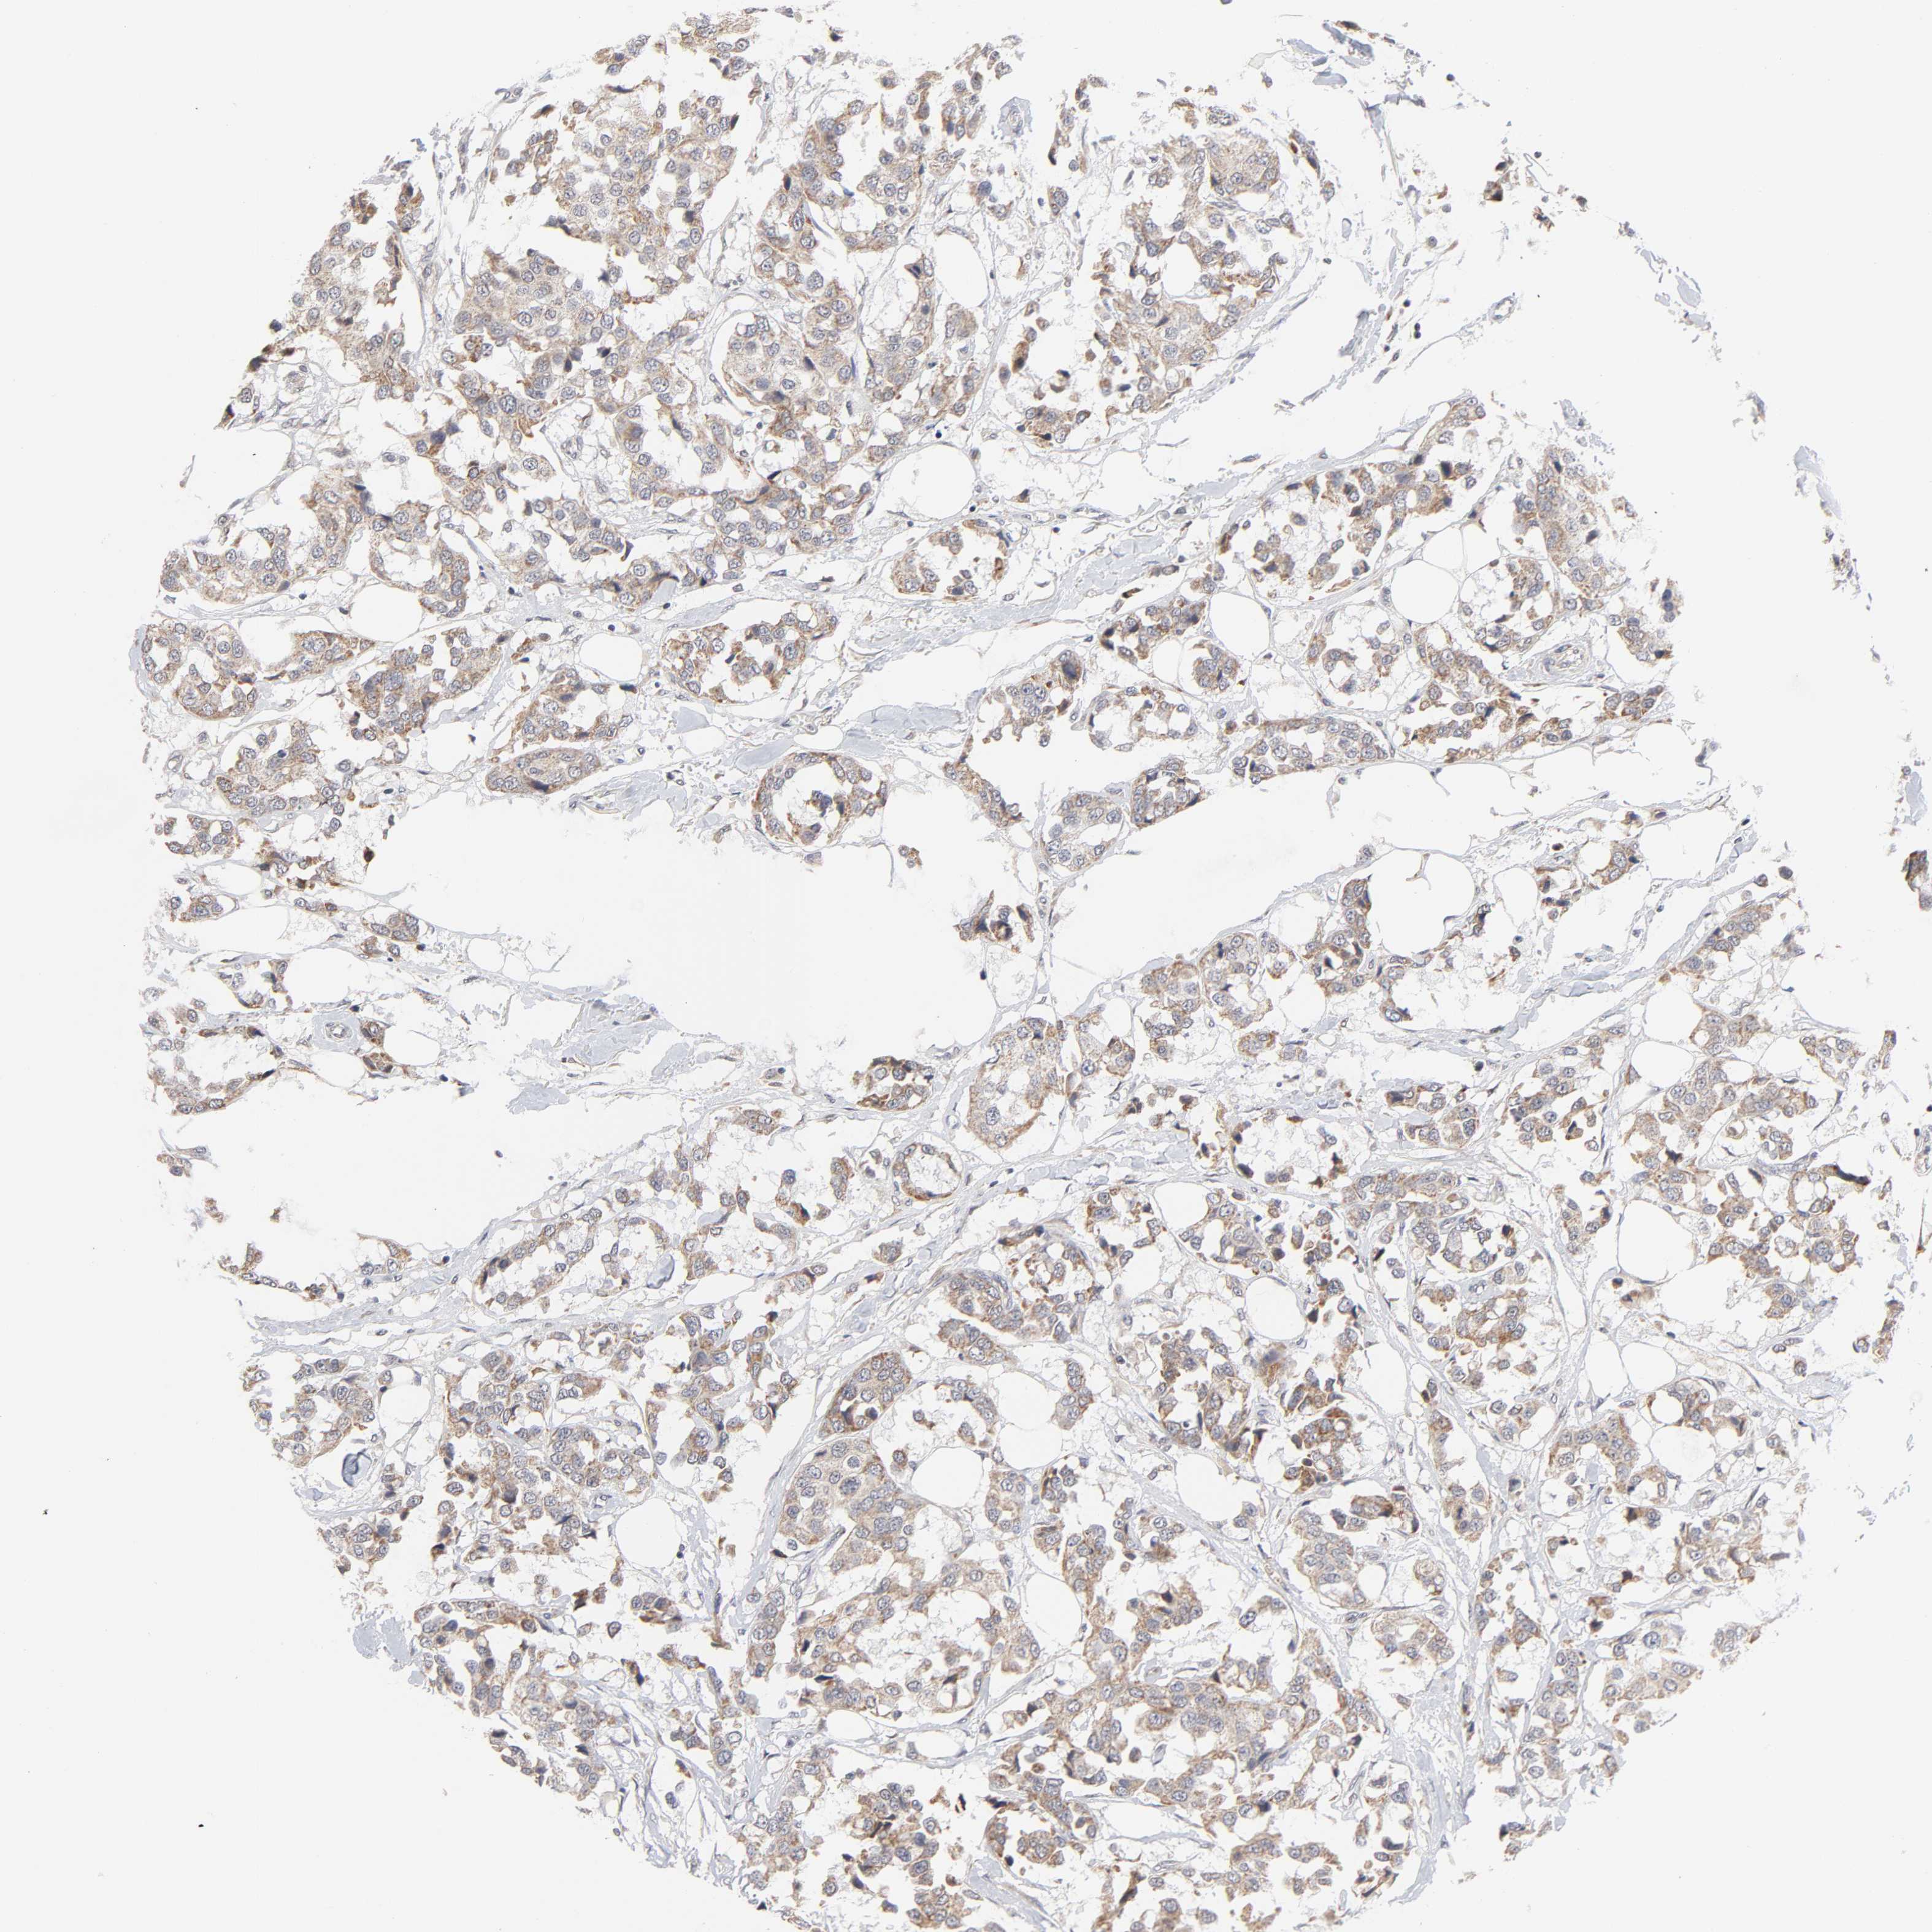

CANCER BREAST CANCER Show tissue menu

BRCA TCGA BRCA VALIDATION PROTEIN EXPRESSION

AUH is not prognostic in Breast Invasive Carcinoma (TCGA)